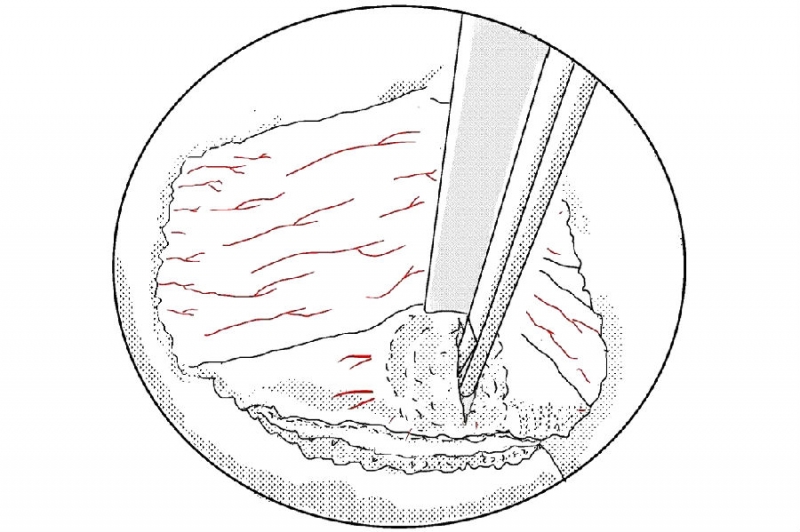

1. 建立通道后的多裂肌三角“地板解剖”;

2. 大刀头清理软组织;

3. 使用4mm金刚砂磨钻将椎板下缘及下关节突内缘磨薄;

4. 使用椎板咬骨钳继续向近端咬除椎板直至黄韧带近端止点;